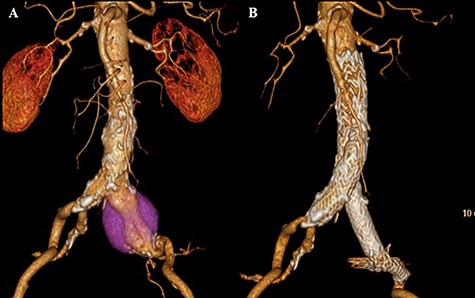

A 76-year-old man was incidentally diagnosed with a left CIAA by abdominal ultrasonography, with computed tomography (CT) demonstrating a left CIAA measuring 4.5 cm in diameter (Fig. 1A). The patient was referred to our hospital for surgical treatment. He had a medical history of liver cirrhosis and traumatic abdominal injury. Thus, he underwent EVAR using a GORE EXCLUDER AAA Endoprosthesis to embolize the left internal iliac artery. The postoperative course was uneventful, and postoperative CT showed no endoleak (Fig. 1B). Follow-up CT scans at 6-month, 1-year and 2-year intervals post-EVAR revealed a reduction in the size of the aneurysmal sac. However, the 3-year interval CT demonstrated an increase in the sac size (Fig. 2A). Contrast-enhanced CT and angiography revealed no endoleak but showed a dilatation of the CIAA. Therefore, the patient underwent open aortic repair of the CIAA.

CT scan showing left CIAA (A). Contrast-enhanced CT demonstrating no endoleak after EVAR using a GORE EXCLUDER AAA Endoprosthesis to embolize the left internal iliac artery (B).

CT scan showing the increasing sac size of left CIAA with no endoleak (A) and aortic replacement with a Y-shaped vascular prosthesis performed with complete explantation of the endograft (B).

The infrarenal aorta up to the right common iliac artery and the left external iliac artery were exposed via a retroperitoneal approach. Proximal control was achieved by clamping midway between the renal arteries and the aortic bifurcation, and distal control was achieved by inserting an occlusion balloon into the right common iliac artery and clamping the left external iliac artery. The sac of the CIAA was opened, and many thrombi were noted around the stent graft. No backbleeding of the lumbar arteries or junctional bleeding of the stent was detected, and the entire endograft was removed easily. Abdominal aortic replacement with a Y-shaped vascular prosthesis (J Graft SHIELD NEO, bifurcated vascular prosthesis) was performed (Fig. 2B). Proximal and distal anastomoses were performed at the level of midway between the renal arteries and the aortic bifurcation where the endograft was fixed, and at the level of the right common and left external iliac arteries, respectively.